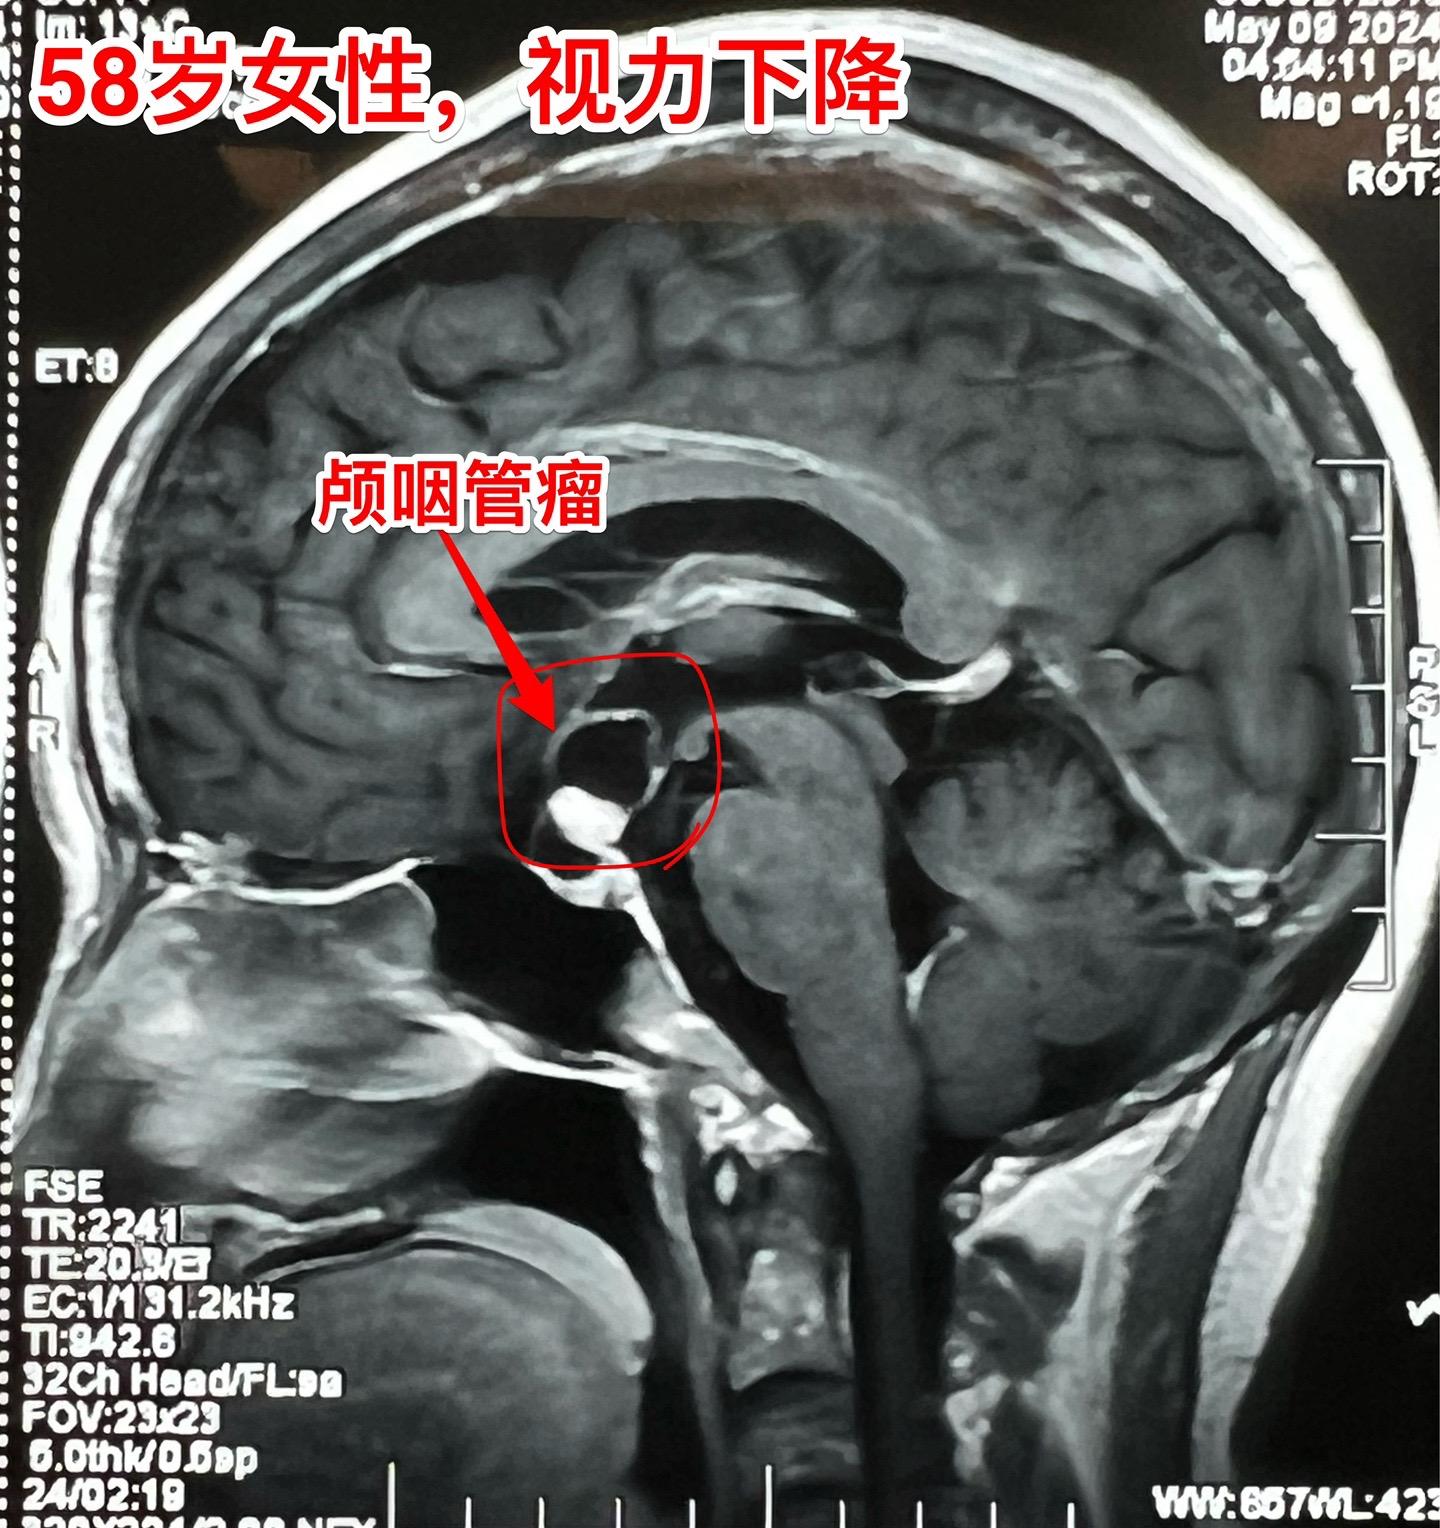

58岁女性视力下降。这是典型的颅咽管瘤。 这样的颅咽管瘤更适合翼点入路:瘤位于鞍上池内,直径约2厘米,乳头型颅咽管瘤。 病人的左眼视力更差,所以选择经左侧翼点入路。肿瘤得到完全切除。视力下降

58岁女性视力下降。这是典型的颅咽管瘤。 这样的颅咽管瘤更适合翼点入路:瘤位于鞍上池内,直径约2厘米,乳头型颅咽管瘤。 病人的左眼视力更差,所以选择经左侧翼点入路。肿瘤得到完全切除。颅咽管瘤视力下降